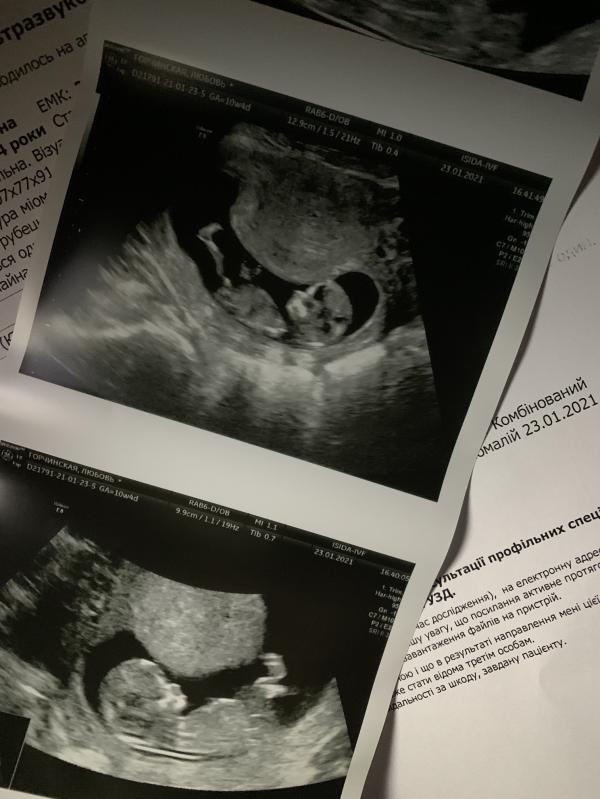

Вообщем приехали сегодня на УЗИ в Исиду,10 недель.А оказалось что 12,5.Сказали что торчит что то,но не уверенны что мальчик.Кто там скидывал как определить по положению ?)